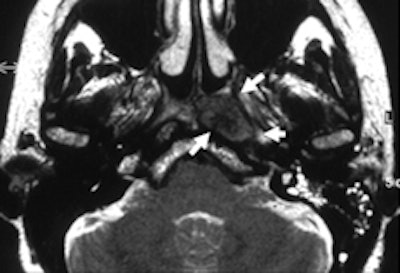

Real-time imaging showed regular opening of the right eustachian tube during Valsalva maneuver (open arrows, right image: neutral position; left image: Valsalva maneuver). The left tube opens only in the anterior part but not in the middle part, due to compression from the tumor (arrows).Krombach was based at University Hospital, University of Technology (RWTH) in Aachen, Germany when she conducted the head and neck study, along with radiologists Anna Luekens and Dr. Rolf Guenther from RWTH and Dr. Ercole DiMartino from the department of otolaryngology and head and neck surgery at DIAKO Ev. Diakonie-Krankenhaus in Bremen, Germany. The group's work was published online first by European Radiology on 13 October.

T2-weighting shows sinusitis with swelling of the mucosa. Real-time imaging demonstrates that both eustachian tubes do not open during Valsalva maneuver (right image, arrows).It was possible to evaluate the opening of the eustachian tube during the Valsalva maneuver in all patients. Within the same examination, an underlying problem was identified and its extent delineated in 14 of the 16 patients. In all patients, the anatomical landmarks and structures were clearly depicted and differentiated from pathological abnormalities in the T2-weighted sequence. Involvement of the anatomical structures could be assessed, but the osseous part of auditory tube was depicted with less good image quality than the other parts. In this region, the amount of soft tissue is small and consists only of the mucous membrane, connective tissue, and the periosteum.